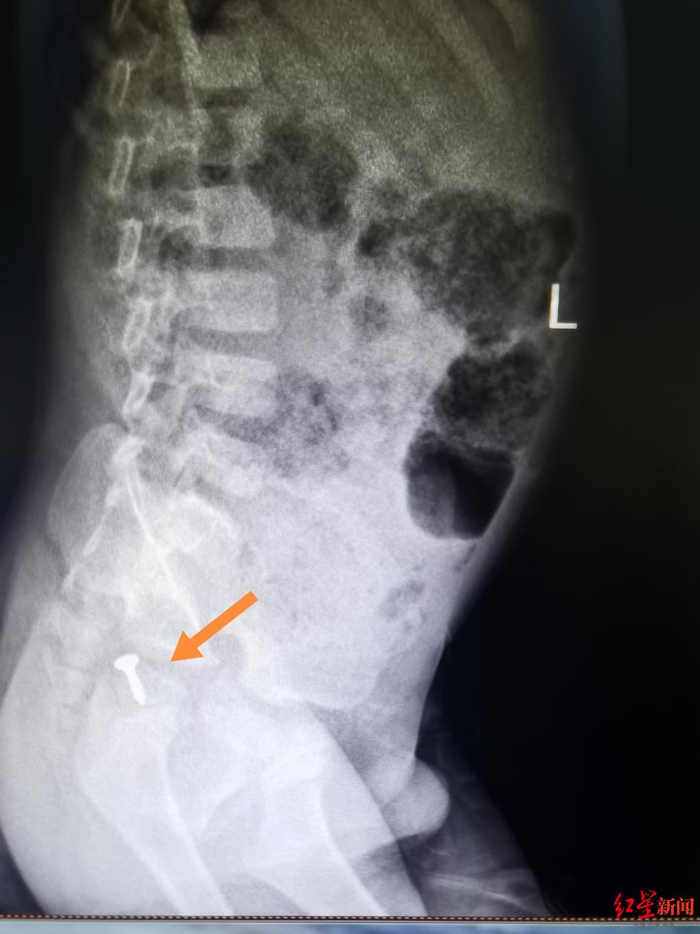

果然,在第二次就诊复查后,螺丝钉的位置比第一次就医时下降了一些。“2月4日复查时,我发现螺丝钉已经接近了乙状结肠的位置,很快就会到直肠,判断应该很快就会随着排便排出。”覃道锐说,家长按照医嘱给孩子使用了开塞露,刺激排便,果然,很快家长就带着排出的螺丝钉返回门诊:“医生你看,真的拉出来了。”

▲2月4日,螺丝钉已经接近乙状结肠位置